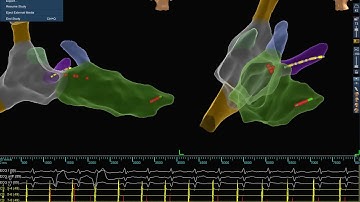

Rotating Pacemaker Fluoroscopic Video